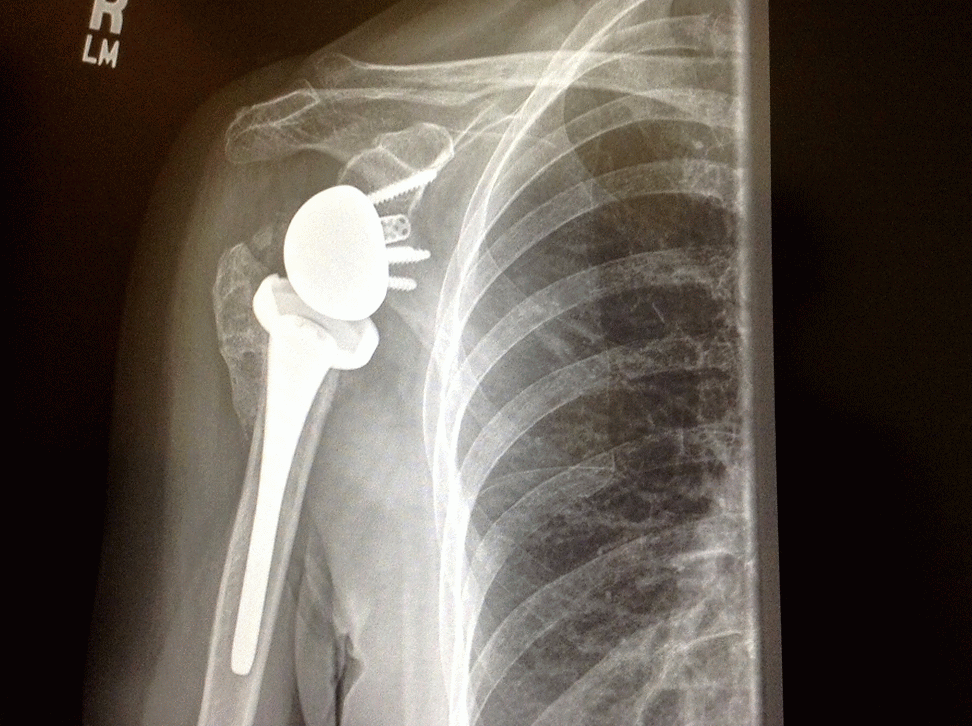

3d rendered illustration of a shoulder replacement Stock Photo Alamy Shoulder Replacement Surgery Video Animation Total shoulder replacement (tsr), also known as total shoulder arthroplasty (tsa) or anatomic total shoulder replacement, is a surgery to. This animation explains total shoulder replacement, a surgical procedure in which parts of an arthritic or damaged shoulder joint are. Watch a medical animation of reverse shoulder replacement surgery, a procedure for patients with rotator cuff tears. Understand.com® is excited. Shoulder Replacement Surgery Video Animation.